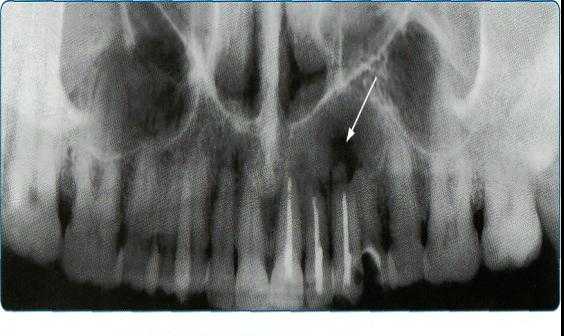

корня зуба. Нередко корень зуба проникает в полость кисты. В структуре фолликулярной кисты всегда определяется коронковая часть непрорезавшегося, как правило, полностью сформированного зуба. На рентгенограммах изучаются такие симптомы: форма и размер кистозной полости, локализация, состояние кортикальных пластин челюсти, однородность структуры, наличие внутриполостных перегородок, степень деструкции костей и состояние зубов в проекции кисты. Контактные внутриротовые рентгенограммы обладают достаточной информативностью для определения кист небольших размеров и оценки состояния пародонта. При кистах больших размеров они не дают полной информации о рентгенологических признаках, а что особенно важно, не позволяют в полной мере оценить окружающие области, например верхнечелюстной синус. На рентгенограмме происходит суммация теней различных образований челюстно-лицевой области, что создает трудности при изучении рентгенограмм Радиовизиография с последующим компьютерным анализом оптической плотности изображения является диагностически значимым методом для оценки плотности костной ткани. Ее проводят для контроля процесса остеорегенерации в области костного дефекта после оперативного вмешательства.

Компьютерный томограф позволяет на основании стандартных изображений в аксиальной плоскости моделировать изображения лицевого отдела головы в любых произвольных проекциях для улучшения пространственной визуализации. Современные компьютерные томографы, имеют высокую разрешающую способность за счет возможности создания тонких срезов тканей. С применением оптической денситометрии удается определить структуру костной ткани в очаге деструкции, структуру содержимого кистозной полости, объективно оценить динамику восстановления костной ткани в патологическом очаге в процессе лечения. На компьютерном томографе с использованием трехмерной реконструкции можно установить «причинный» зуб, определить форму, истинные размеры кисты, направление ее роста и характер взаимоотношения с окружающими тканями. С помощью КТ может быть проведена дифференциальная диагностика между одонтогенной интрасинусальной кистой и истинной кистой пазухи путем выявления костной перегородки, отделяющей полость истинной кисты от полости пазухи, отсутствию связи с корнями зубов. МСКТ высокоэффективна в диагностике кист, но несет значительную лучевую нагрузку. МСКТ также требует оптимизации алгоритмов обследования и интерпретации полученных изображений в контексте стоматологической и челюстно-лицевой специфики с акцентом на определенные анатомические структуры. Перспективным направлением лучевой диагностики являются конусно-лучевые компьютерные томографы. Трехмерная конусно-лучевая компьютерная томография значительно увеличила возможности дифференциальной диагностики в специализированной амбулаторной стоматологии и челюстно-лицевой хирургии. В основе конусно-лучевых томографов используется рентгеновский луч конусной формы. Рентгеновский луч проходит через ограниченный объем ткани, с размером ребра куба не более 15 сантиметров, в итоге получается первичное трехмерное изображение высокого разрешения при минимальной дозе облучения. Конусно-лучевой томограф дает цифровое изображение высокого разрешения изучаемого объекта в трех плоскостях. С помощью конической формы луча толщина среза может быть установлена от 0,125 мм до 2 мм. При этом лучевая нагрузка на пациента в 6-10 раз меньше, чем при проведении стандартной спиральной компьютерной томографии.

Разрешающая способность у конусно-лучевого компьютерного томографа при визуализации корневых каналов зубов и костных структур альвеолярных частей не имеет аналогов. Конусно-лучевой компьютерный томограф позволяет проводить реконструкцию срезов под любым углом к зубной дуге. Благодаря этому лучевой диагност получает более полноценную и четкую визуализацию изображения. При лучевой диагностике патологии лицевого отдела головы особое внимание следует уделять оценке целостности костных стенок полости носа и верхнечелюстной пазухи, состоянию слизистой оболочки ЛОР-органов, наличию или отсутствию патологических соустий между полостью рта и носовой полостью через свищевой ход. Точность визуализации вышеперечисленных признаков влияет на выбор тактики лечения и прогноз в послеоперационном периоде.